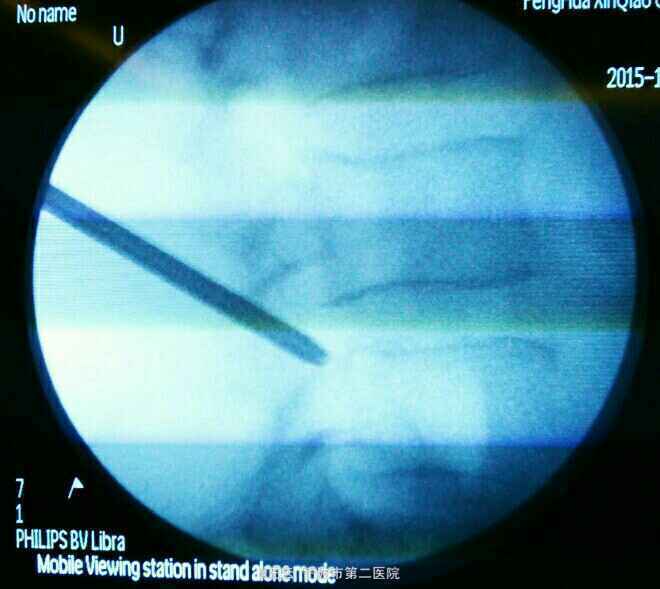

诊断:L3/4椎间盘脱出 治疗:经椎间孔入路椎间孔镜下髓核摘除,射频消融

术后症状立刻缓解,直腿抬高实验80度阴性。